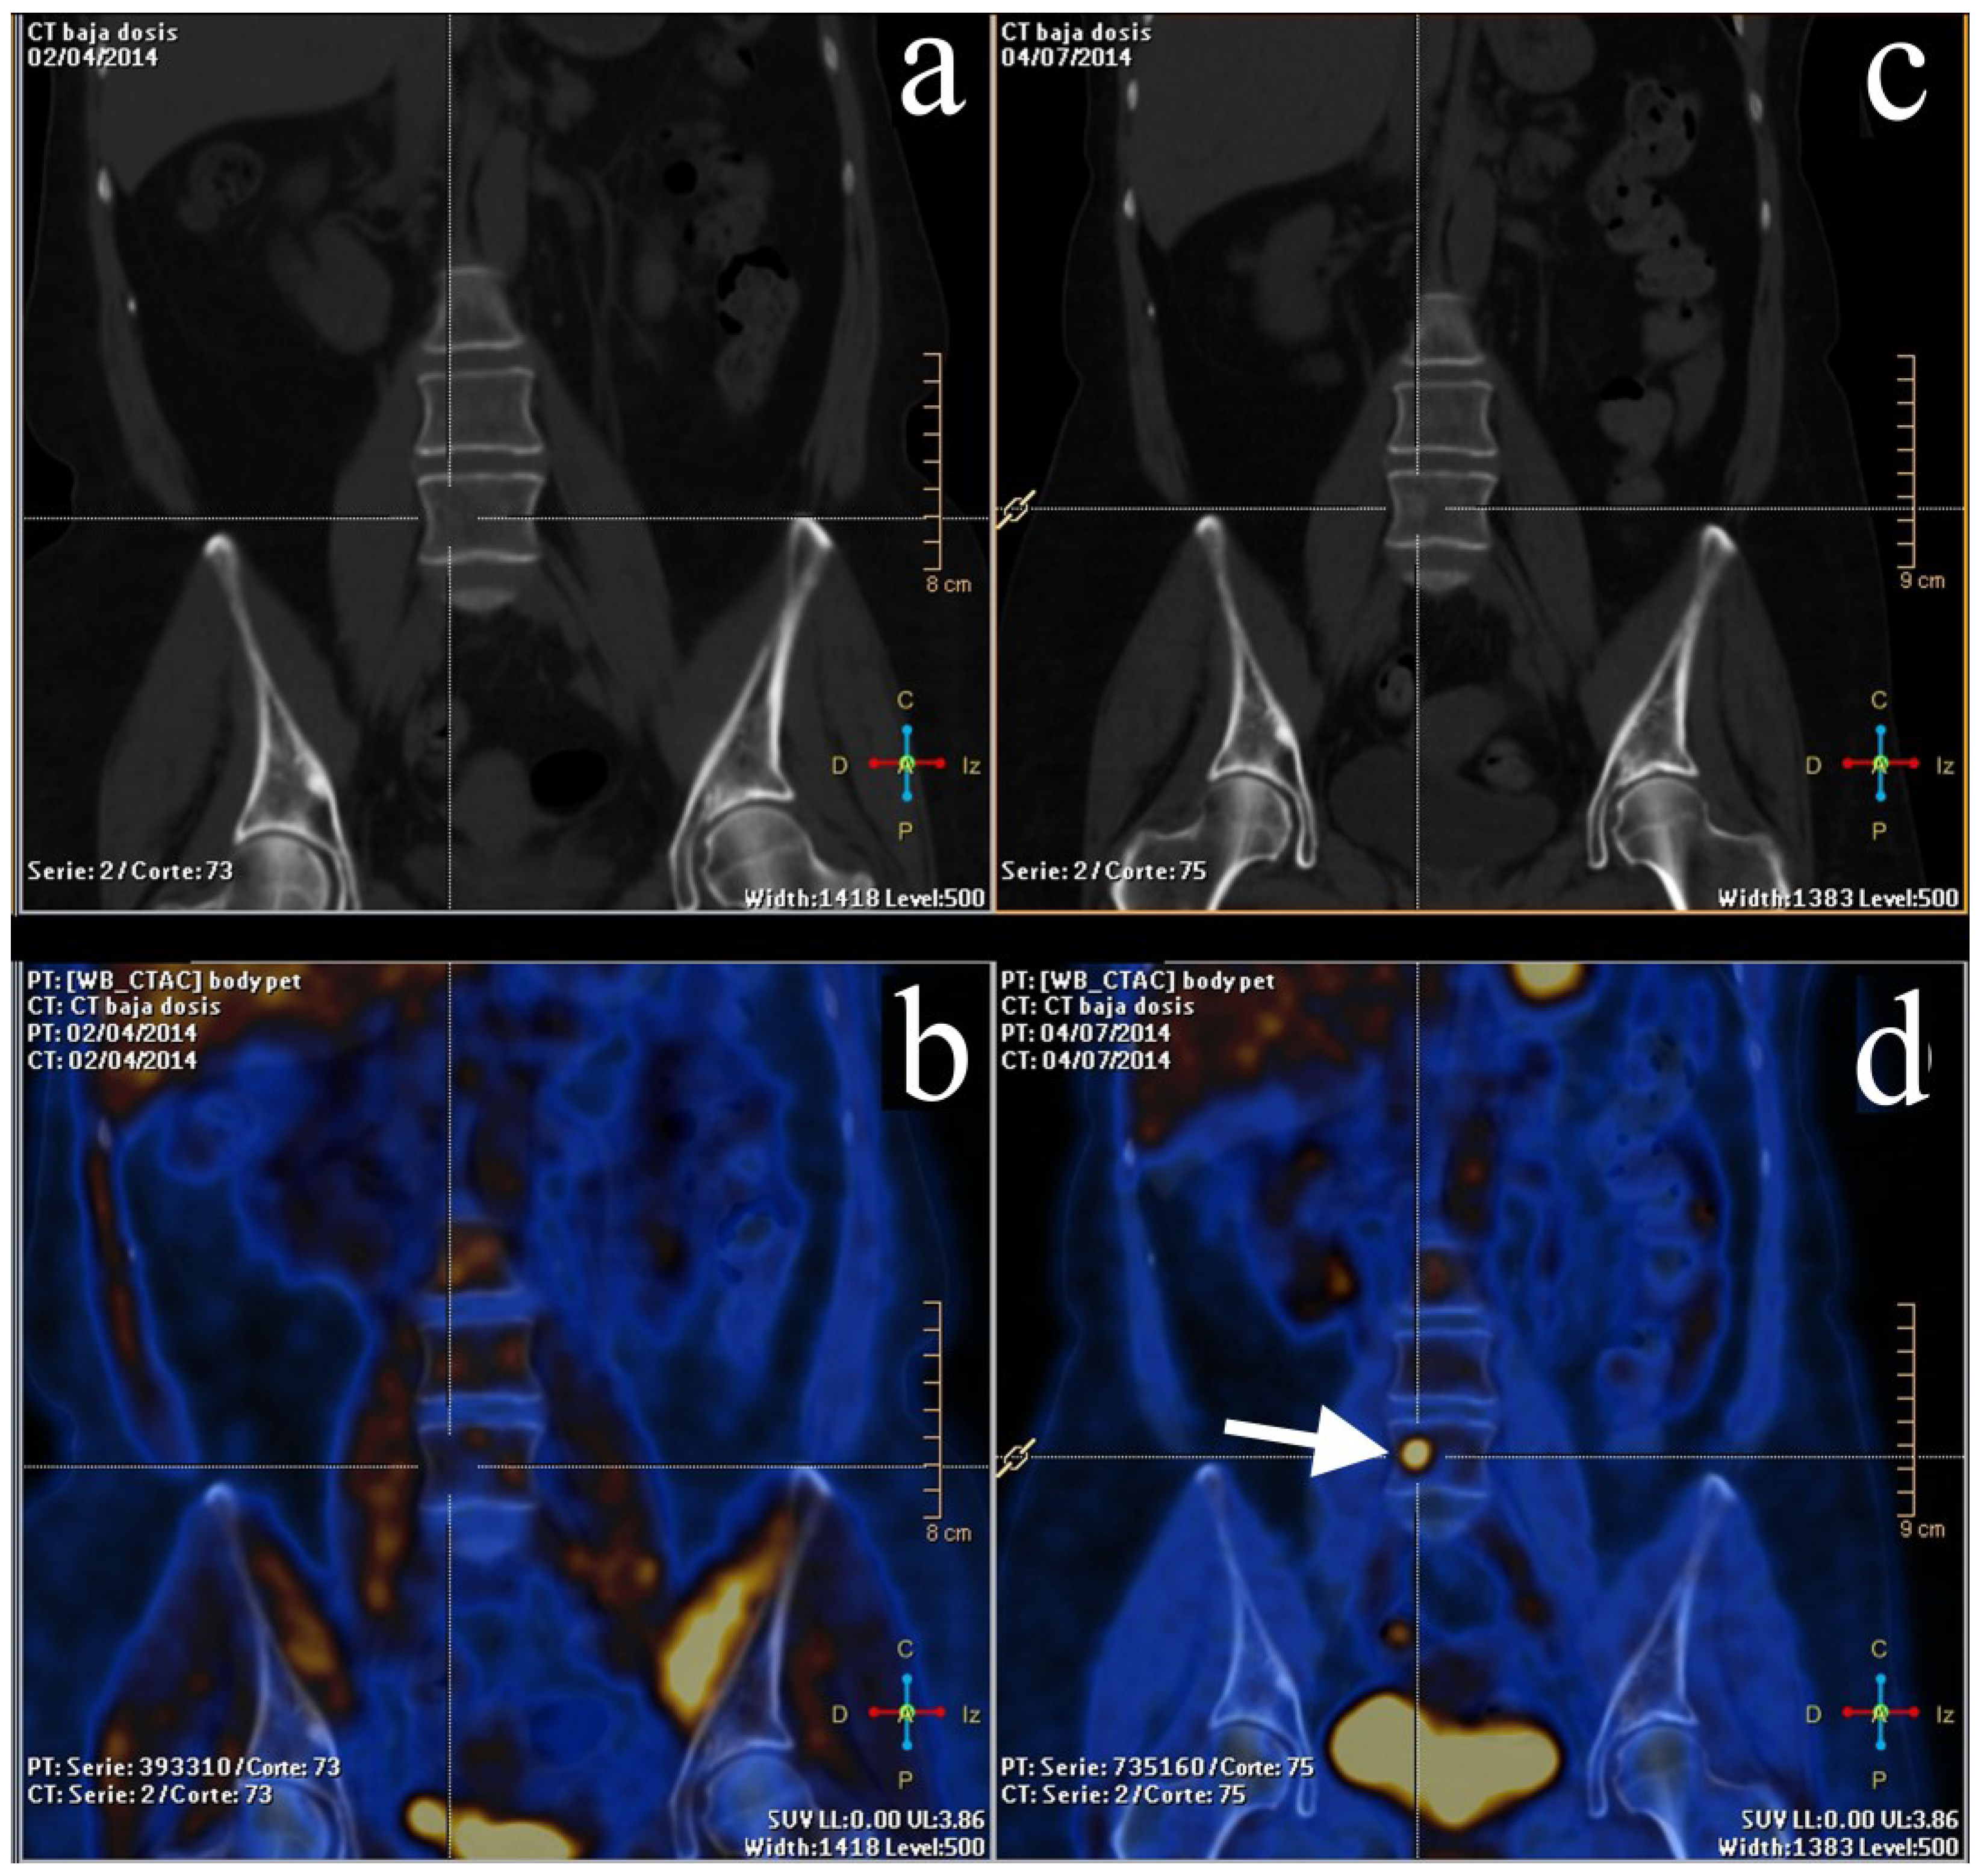

2.2. Staging and Re-Staging

2.3. Treatment Response Evaluation